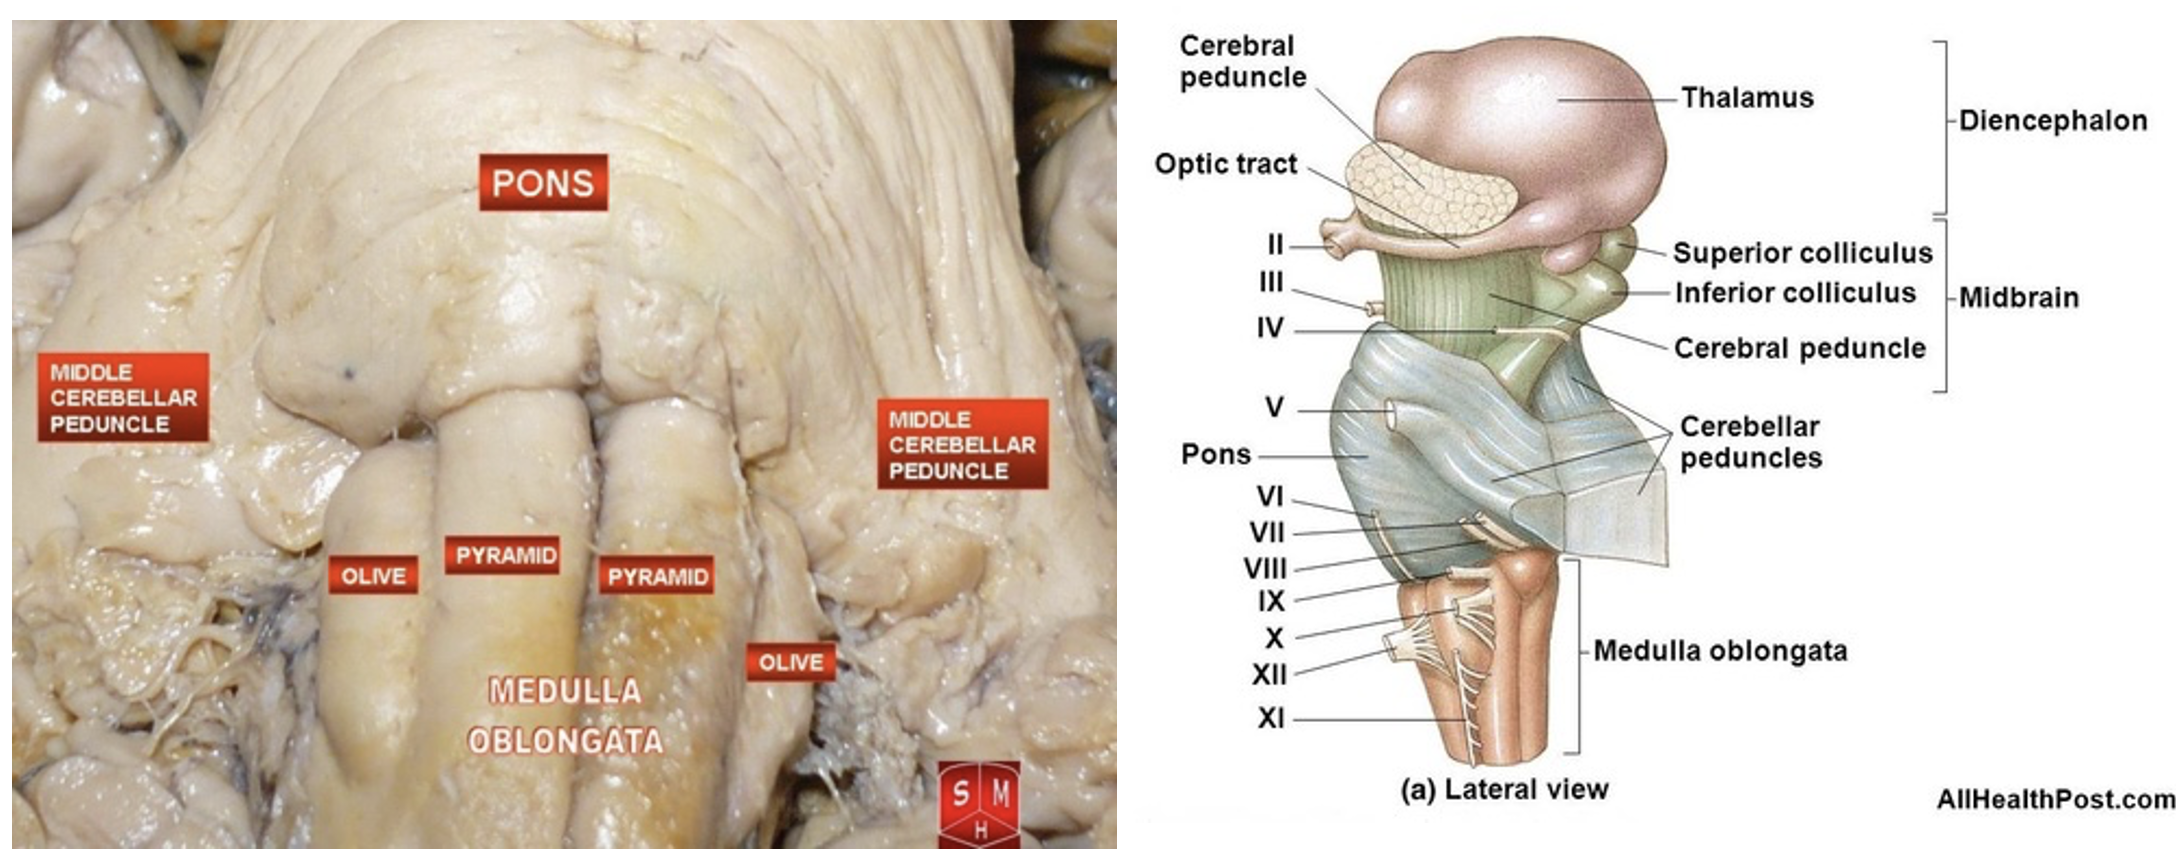

Brain stem

Olive

Pyramids

Mid brain

Pons

Medulla oblongata

What information is transmitted via each peduncle?

Middle Cerebellar Peduncle:

Transmits cortico-ponto-cerebellar afferent fibers from the cerebral cortex to the cerebellum via the pons.

Superior Cerebellar Peduncle:

Transmits efferent fibers from the cerebellum to the red nucleus and thalamus, particularly the ventrolateral nucleus, which then influences the rubrospinal and corticospinal systems.

Inferior Cerebellar Peduncle:

Carries both afferent and efferent fibers. Afferents include spinocerebellar, medullocerebellar, and vestibular fibers, while efferents connect the cerebellum to the vestibular and reticular nuclei.

cerebellar peduncles

interpeduncular fossa - space between cerebral peduncles.

Midbrain

Pons

Medulla Oblongata